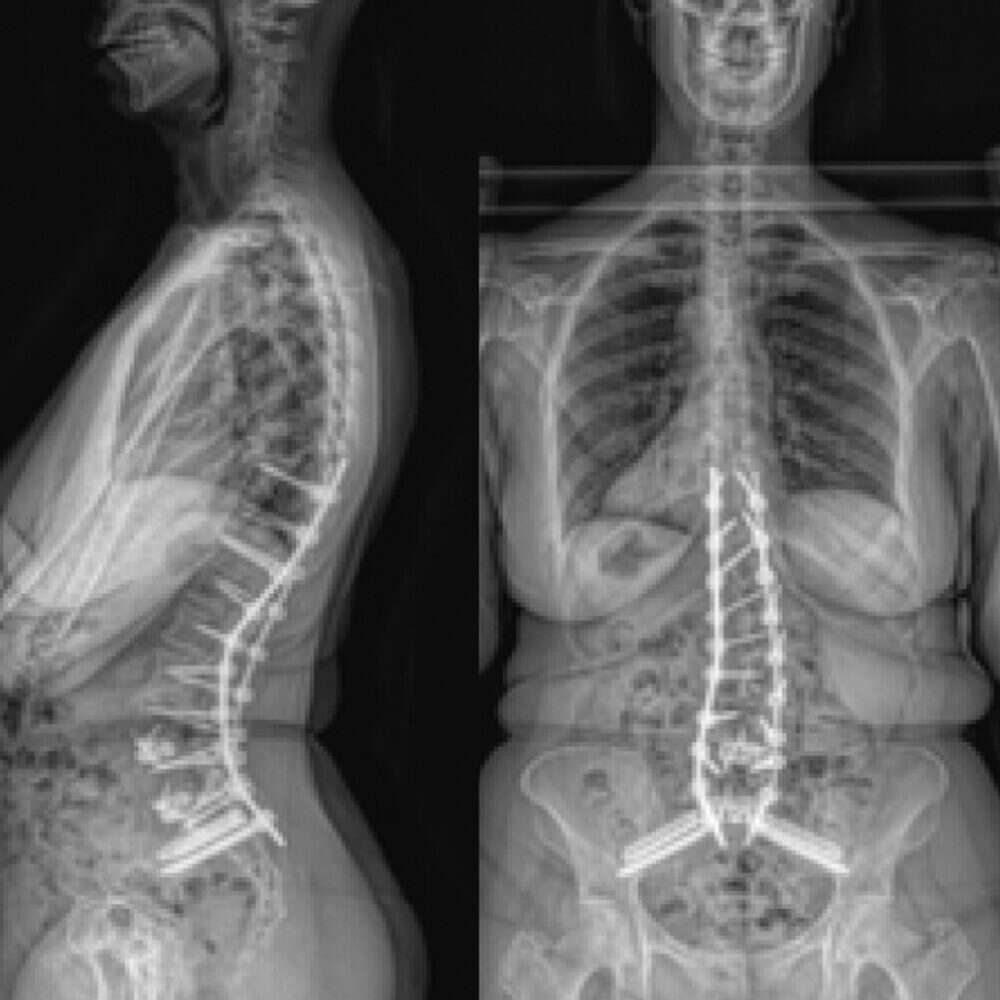

Adult Scoliosis

Patient History:

- Idiopathic adult scoliosis with degenerative changes

- Disabling back and leg pain

- Spondylolisthesis

Surgical Treatment:

- ALIF L5-S1

- T10-pelvis posterior fusion with bilateral placement of S2AI screws and S1AI Bedrock® trajectory iFuse 3D™ implants for SI joint stabilization

Post-op:1,2

- No complaints of back/leg pain at 2-year follow-up

- Back to full-time work as a high-level executive and public speaker